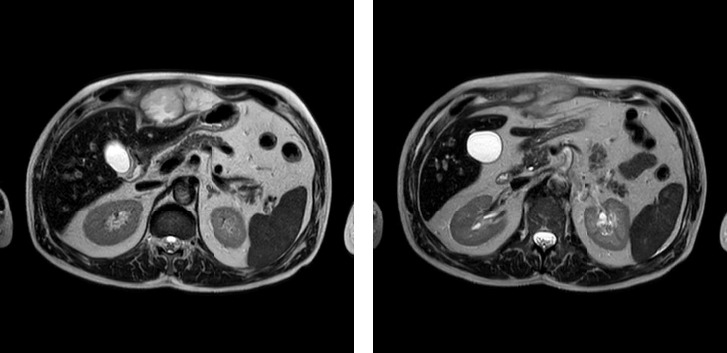

Nocardia species constitute a diverse group of microorganisms classified as aerobic actinomyces. Among these species, many have been implicated as causative agents of severe human infections, particularly in immunocompromised patients, affecting lungs, skin, and nervous system. Here, we described a rare species, identified as Nocardia kroppenstedtii, isolated at the Complex Operative Unit of Virology and Microbiology from the subxiphoid formation and pseudonodular formation in the left leg of a 69-year-old immunocompetent patient, who was hospitalized and treated at the Complex Operative Unit of Internal Medicine and Geriatrics of the University Hospital of Campania "Luigi Vanvitelli" in an antimicrobial diagnostic stewardship context. This rare pathogen was first isolated in 2014 from a bronchoalveolar lavage sample obtained from a lung transplant recipient. Since then, only five cases of clinical interest have been described in literature.